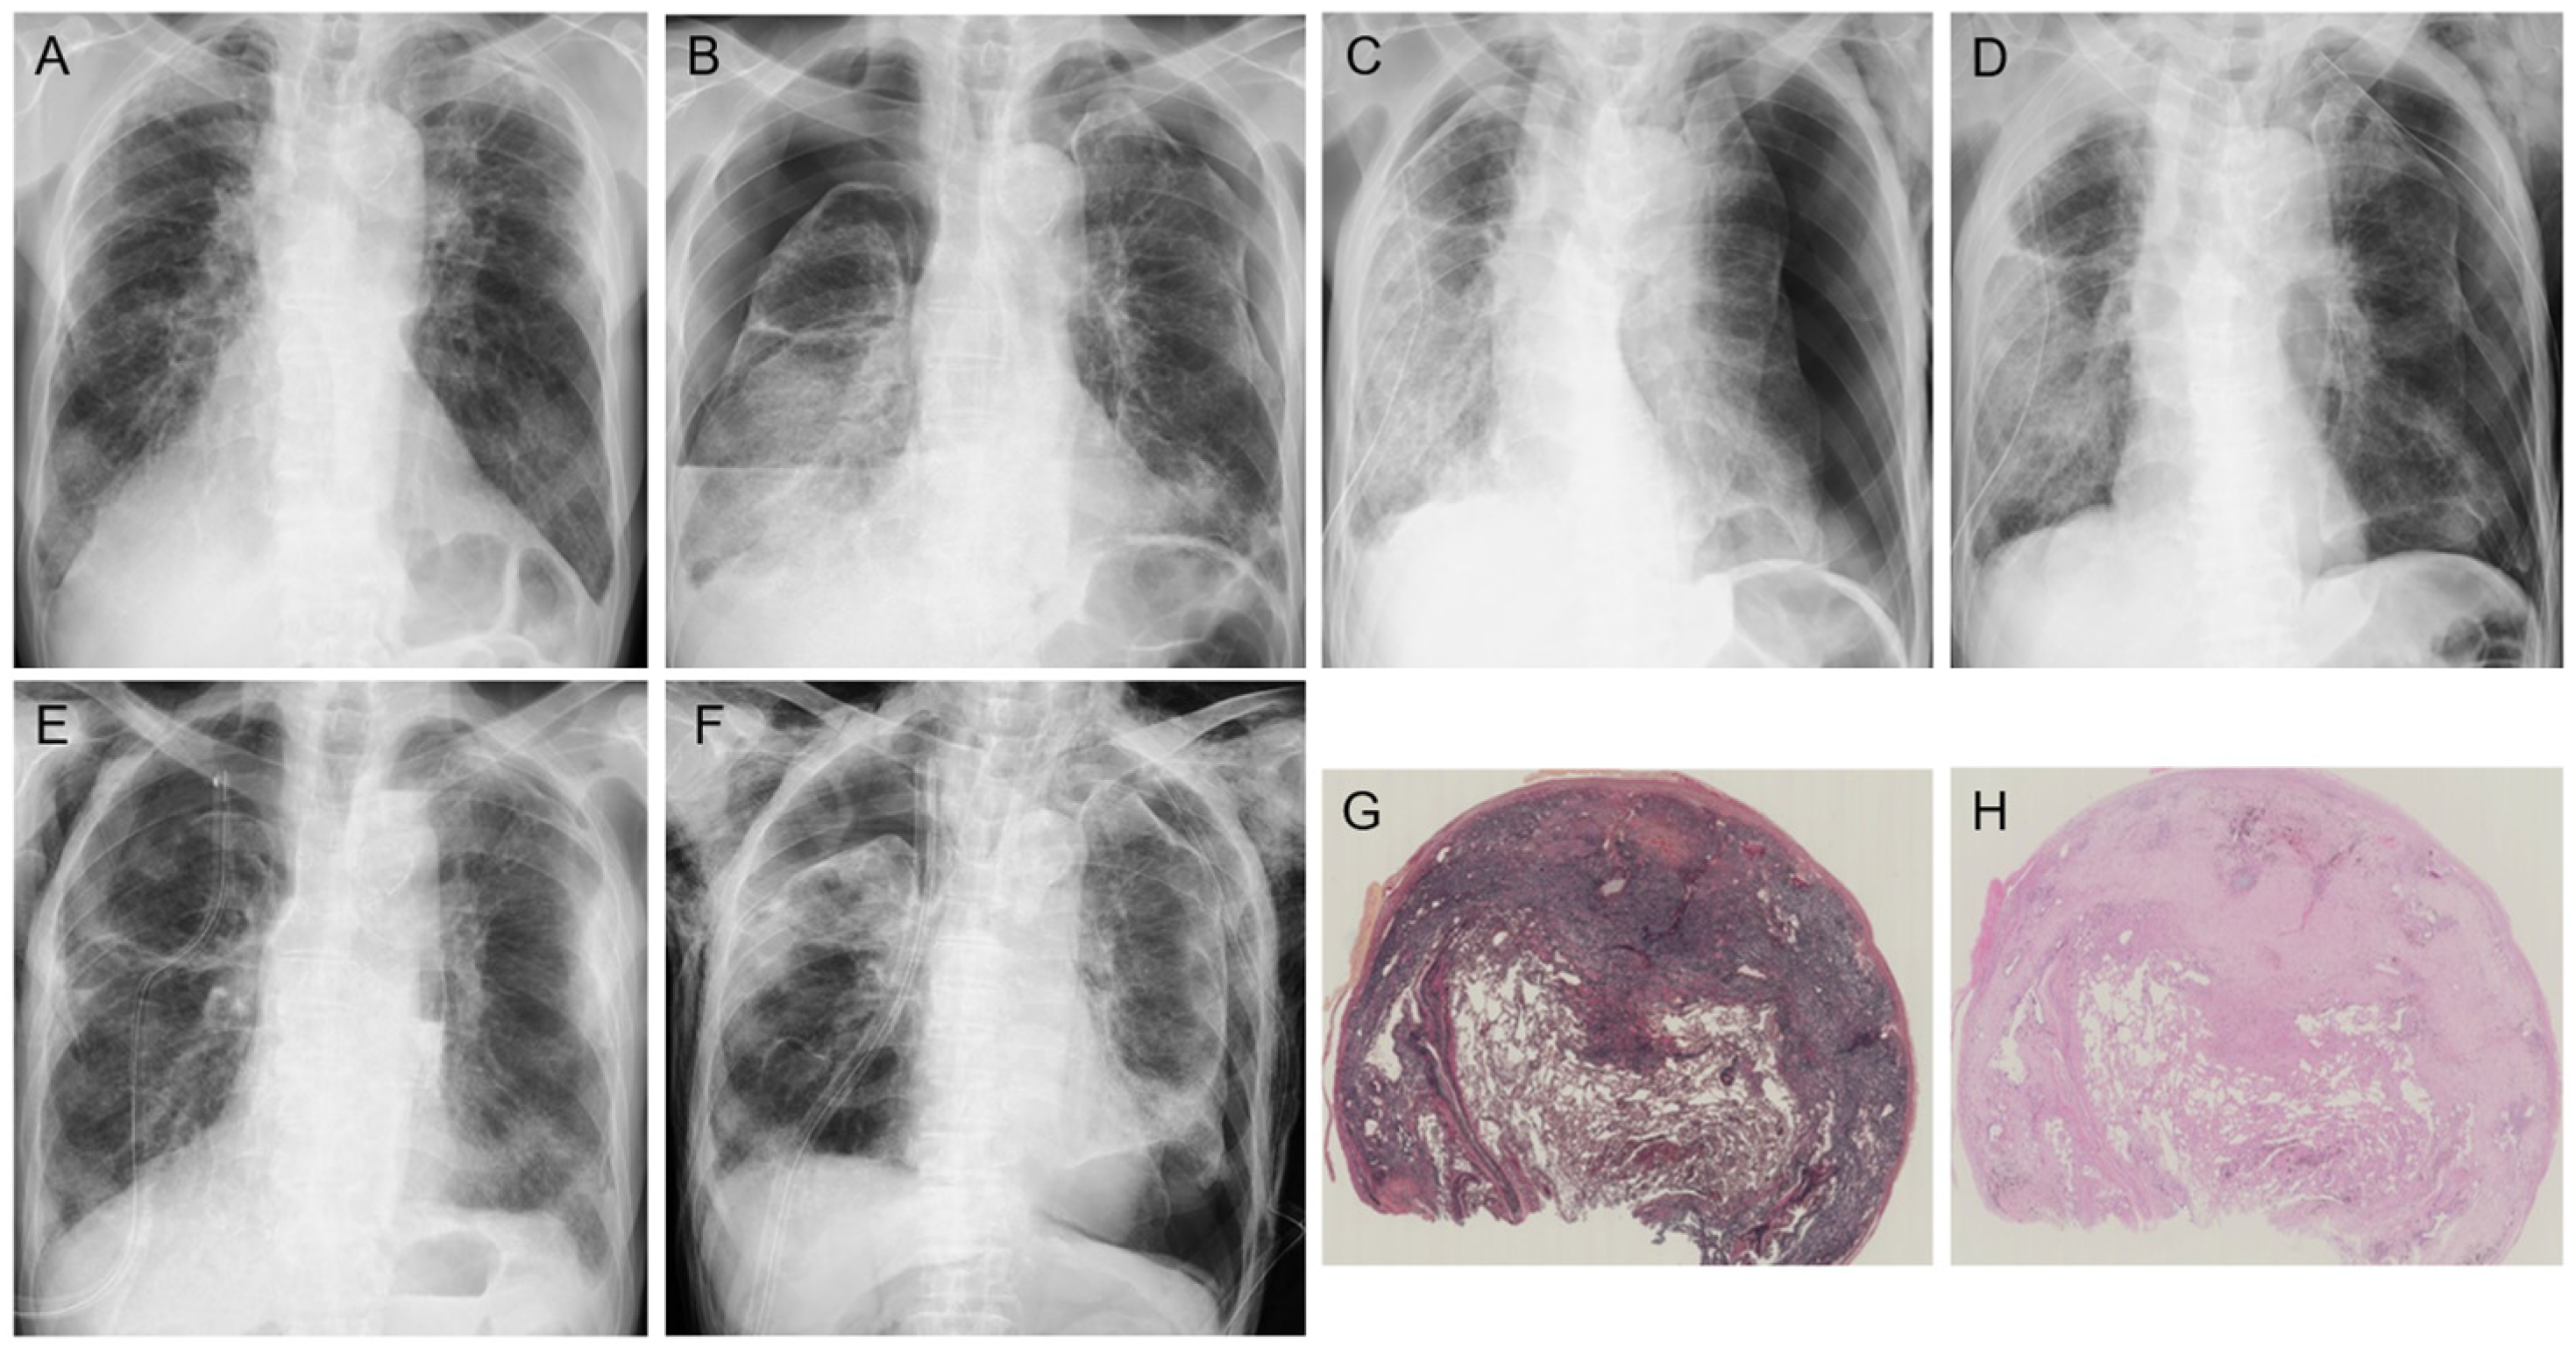

2. Clinical Features